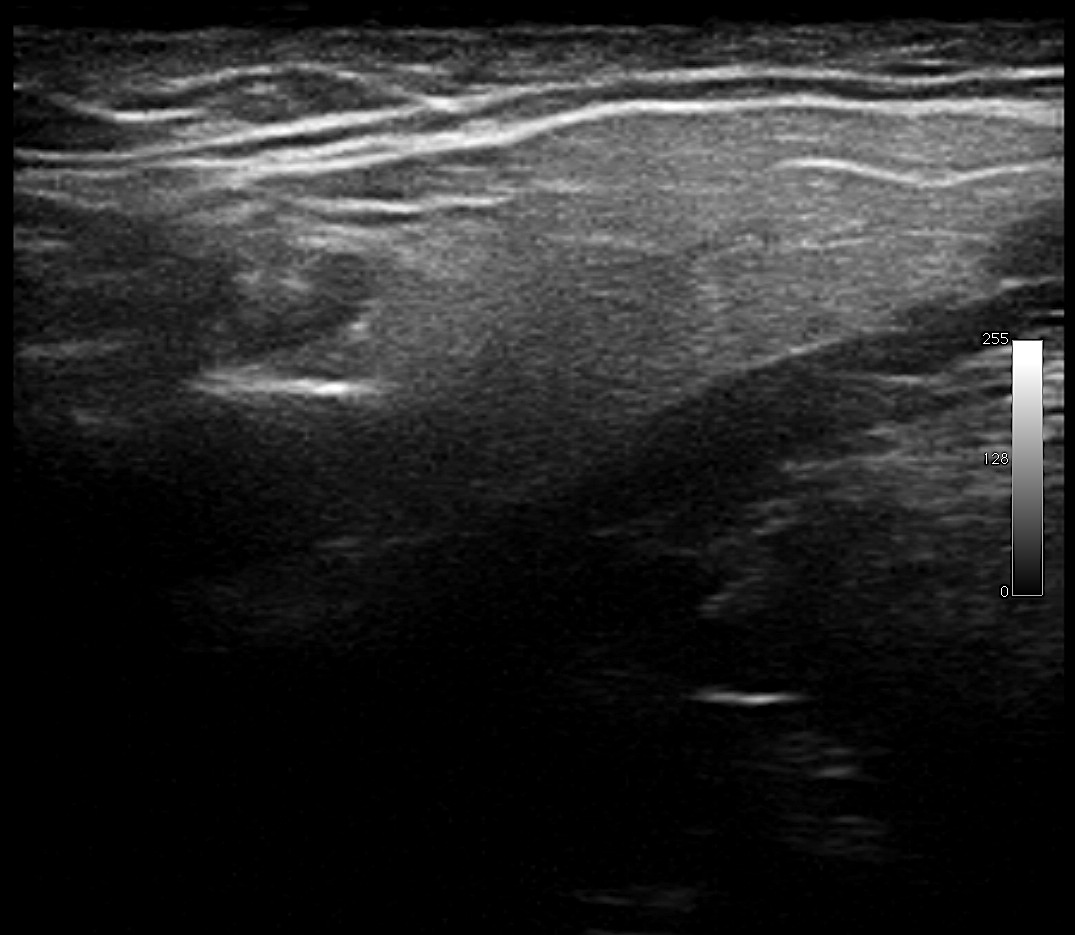

Se realiza ecografía donde se aprecia en teste derecho un quiste epididimal en cabeza y pequeño hidrocele (Imágen 1). En teste izquierdo se observa quiste anecógeno no vascularizado, pequeño quiste para-albuginea y formaciones dilatadas en epididimo no vascularizadas que puedan corresponder por ello a ectasia ductal. (imágenes 2 y 3 y video)